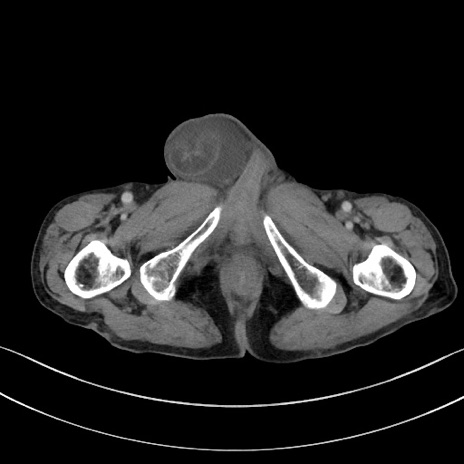

症例3(横断像)

【症例】 70歳代男性

【主訴】右鼠径部腫瘤、疼痛

【現病歴】本日朝より上記主訴あり、受診。

【既往歴】膀胱癌にて膀胱全摘、両側尿管皮膚瘻

【データ】WBC 5600、CRP 0.56